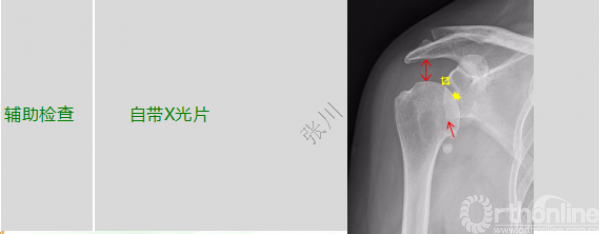

经典病例分享∣骨性Bankart损伤创伤性肩关节不稳定合并肩袖撕裂的治疗

二、初步诊断治疗

1. 完善术前检查

1.影像学评估